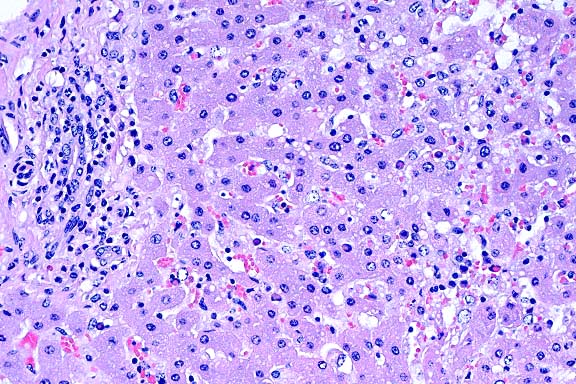

- Case 22-1. Lung. Alveoli are filled with neutrophils

and lined by type II pneumocytes which occasionally contain eosinophilic

intranuclear inclusions bodies.

- Case 22-1. Lung. A syncytial giant cell is accompanied

by abundant foamy alveolar macrophages within and thickening

the septal walls (interstitial pneumonia).

- The giant cell pneumonia seen in this case is typical of

SIVmac-induced giant cell pneumonia and is characterized by extensive

infiltration of alveolar septa and spaces by numerous macrophages

with abundant foamy cytoplasm and multinucleate giant cells of

macrophage-monocyte origin. The interstitial pneumonia with karyomegaly